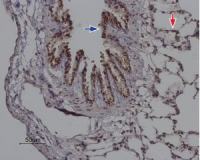

FACS analysis of human peripheral blood lymphocytes using GTX75993 LAIR1 antibody [NKTA255].